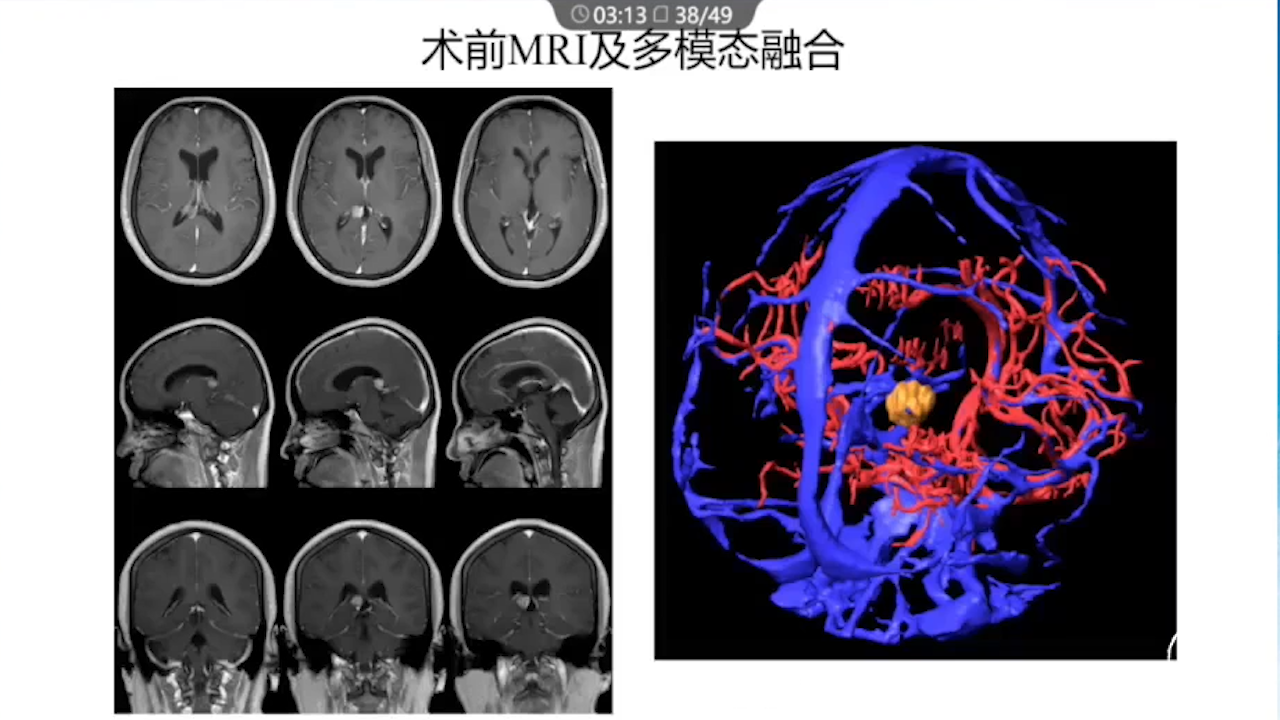

1、术前需要完善的影像学检查、多模态融合及神经导航以进行精确的肿瘤及静脉血管定位。